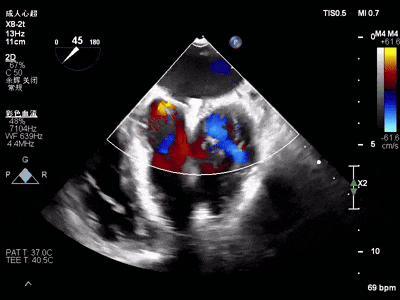

术中超声(关键步骤)

混合性MR,P2脱垂连枷(脱垂范围15mm,连枷间距4mm),腱索断裂

新分型:ACA型,反流2区及两侧,MR 4+,VC:3×14mm

A2:24mm,P2:17mm,AP:38mm,MVA约5.7cm²